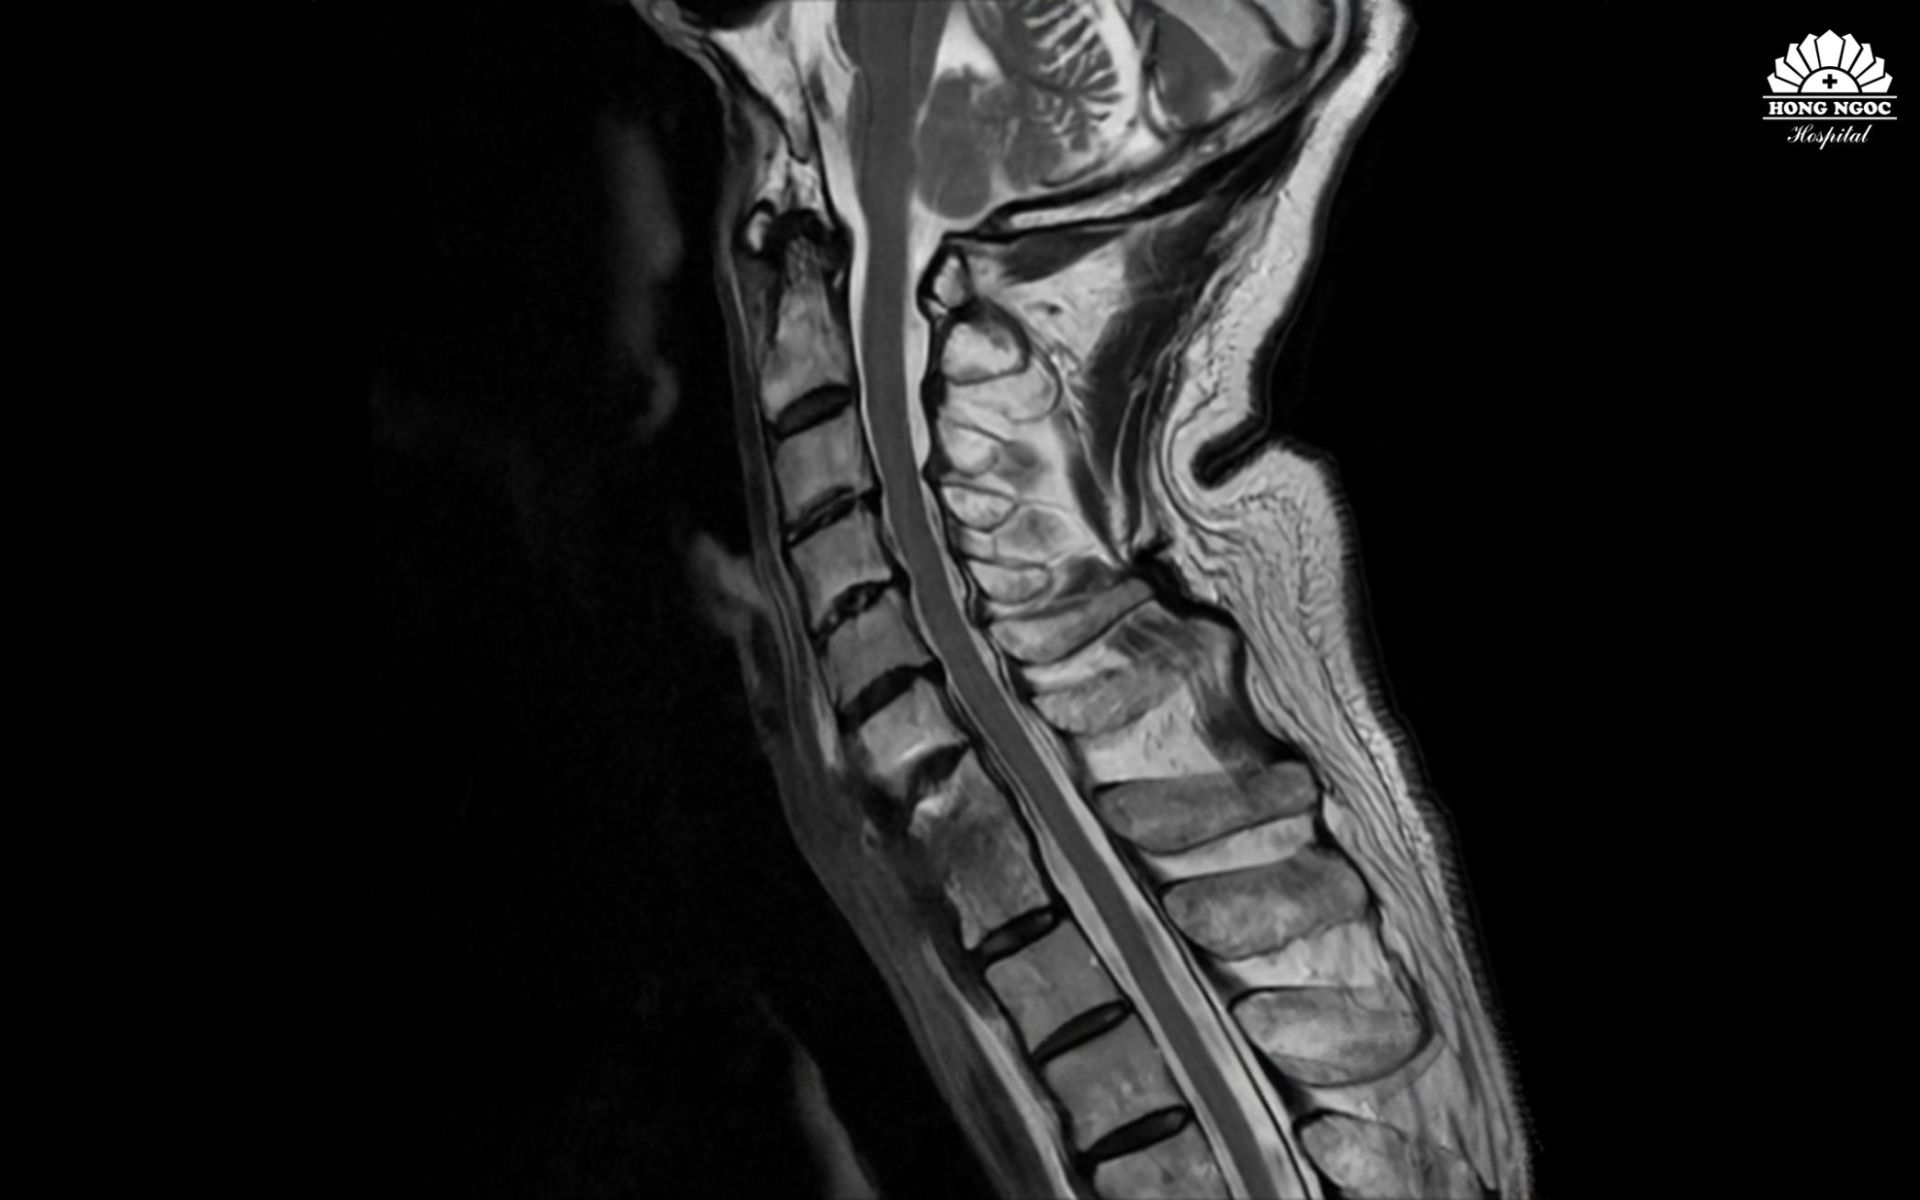

Theo PGS.TS.BS Hà Kim Trung (Chuyên gia phẫu thuật cột sống - Phó Giám đốc Y khoa BVĐK Hồng Ngọc - Phúc Trường Minh) phân tích: Qua kết quả chụp MRI cho thấy, bệnh nhân bị nhiễm trùng cột sống cổ. Theo nhiều nghiên cứu y văn trên thế giới, đây là tình trạng hiếm gặp, chỉ chiếm khoảng 2 - 7% trong tổng số các ca nhiễm trùng cơ xương khớp. Có thể xuất phát từ chấn thương, biến chứng sau phẫu thuật hoặc lây lan qua đường máu. Tình trạng viêm, áp xe phá hủy thân đốt sống và đĩa đệm C7/T1, tạo dải xơ co kéo khiến cổ bệnh nhân luôn trong tư thế gập, không thể xoay, ngửa. Nếu không phẫu thuật sớm, nguy cơ liệt vận động là rất cao.